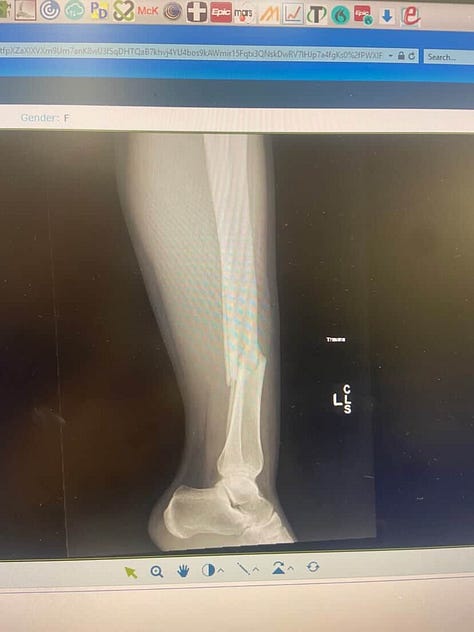

I’m writing this from my bed and current makeshift office in the weeks following a major orthopedic trauma surgery after a complete tibia and fibula fracture sustained during a rugby game.